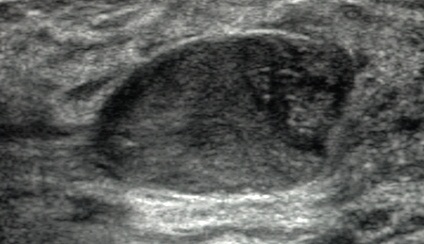

Fibroadenoma

A fibroadenoma is a solid breast mass made up of fibrous tissue and glands.

Fibroadenomas are benign.

Fibroadenomas are the most common benign breast tumor.

Fibroadenomas commonly effect young women.

Fibroadenomas presents as a well-circumscribed, mobile marble-like mass

Additionally, fibroadenomas are estrogen-sensitive, which causes them to grow during pregnancy, and be uncomfortable in certain phases of the menstrual cycle.